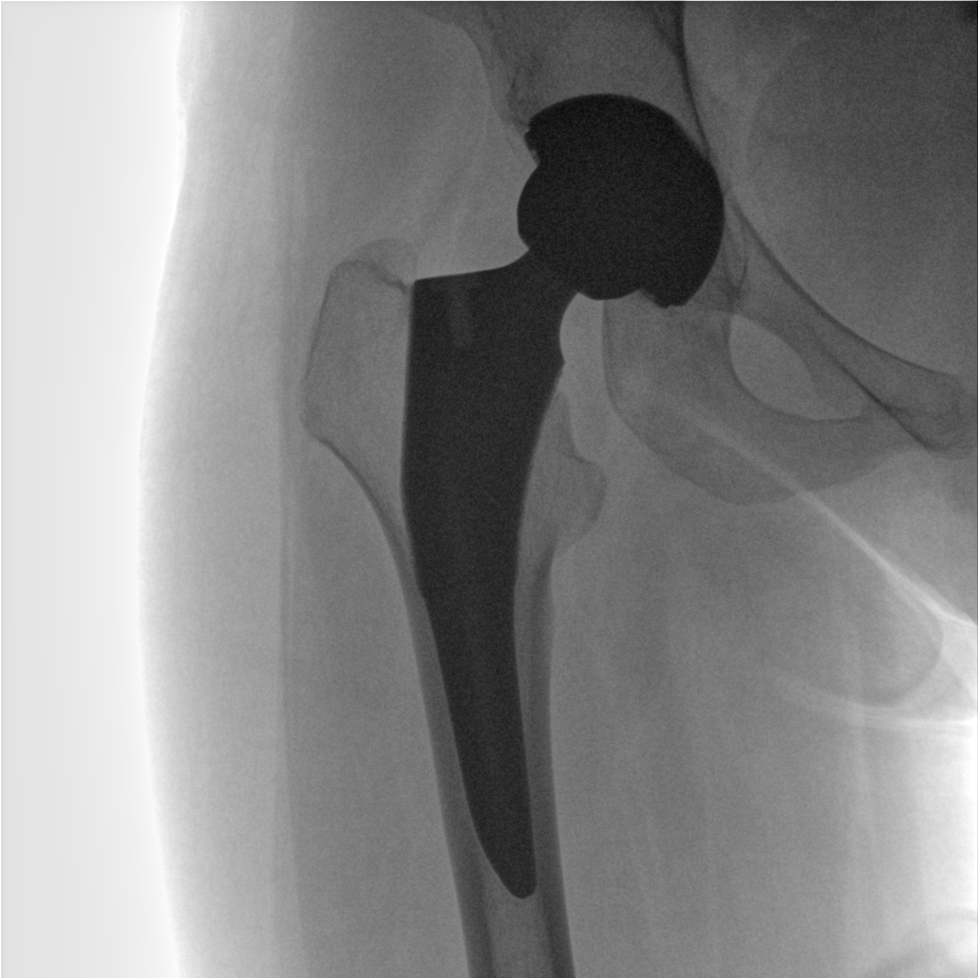

術中三維成像和橫斷面圖像提供多角度的手術診斷信息,輔助醫生進行術中評估判斷,諸如骨折復位情況和內植入螺釘的尺寸和位置,輔助手術更好地完成。

提供更大的術中三維成像視野,采集更多圖像信息,可一次拍全全段頸椎、全段腰椎、七節胸椎、雙側骶髂關節、股骨頭及單側盆骨。